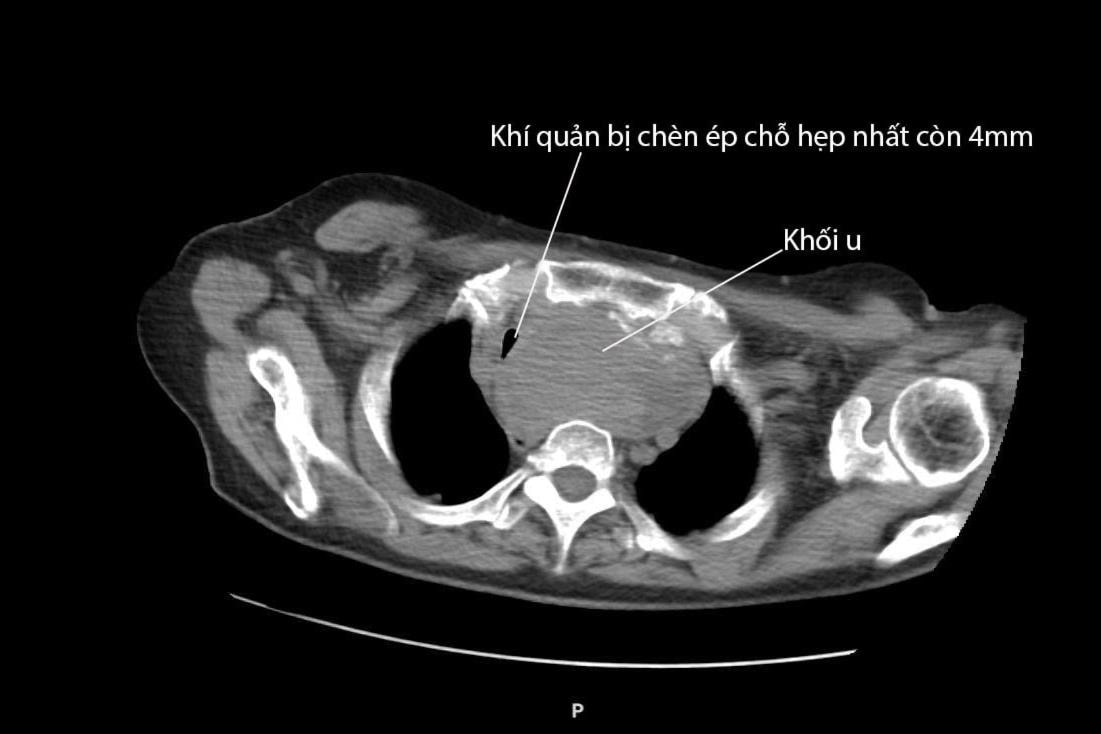

Khí quản bị chèn ép, khiến bệnh nhân thường phải thở gấp, hụt hơi, viêm phổi tái phát do lưu thông khí kém. Ảnh: Bệnh viện cung cấp

Kết quả chụp cắt lớp vi tính cho thấy khối u tuyến giáp cả hai thùy phát triển lớn bất thường, đặc biệt u thùy trái kích thước lên đến 7,5 x 6 x 5 x 4,5 cm lan sâu vào trung thất, chèn ép khí quản sang phải. Thùy phải cũng có khối u kích thước 6 x 3 x 2,5 cm, được xác định là bướu giáp keo đa nhân. Khối u chèn ép nghiêm trọng khiến khí quản bị thu hẹp chỉ còn 4mm – trong khi đường kính trung bình của khí quản người trưởng thành là từ 1,5 đến 2,5cm. Chính vì vậy, bệnh nhân luôn trong tình trạng thở gấp, hụt hơi và viêm phổi tái phát do lưu thông khí kém.